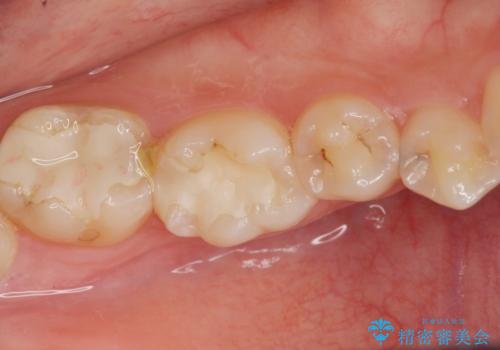

今回は虫歯の治療のみのご希望であったため、掲載している写真の右側2本(口腔内の手前側)を治療していきました。

写真の左側2本(口腔内の奥側)は適合が悪いことが見て取れると思います。

こういった場所は汚れがたまりやすく虫歯のリスクが高くなっているため、適合の良い修復物にやりかえることをお勧めします。